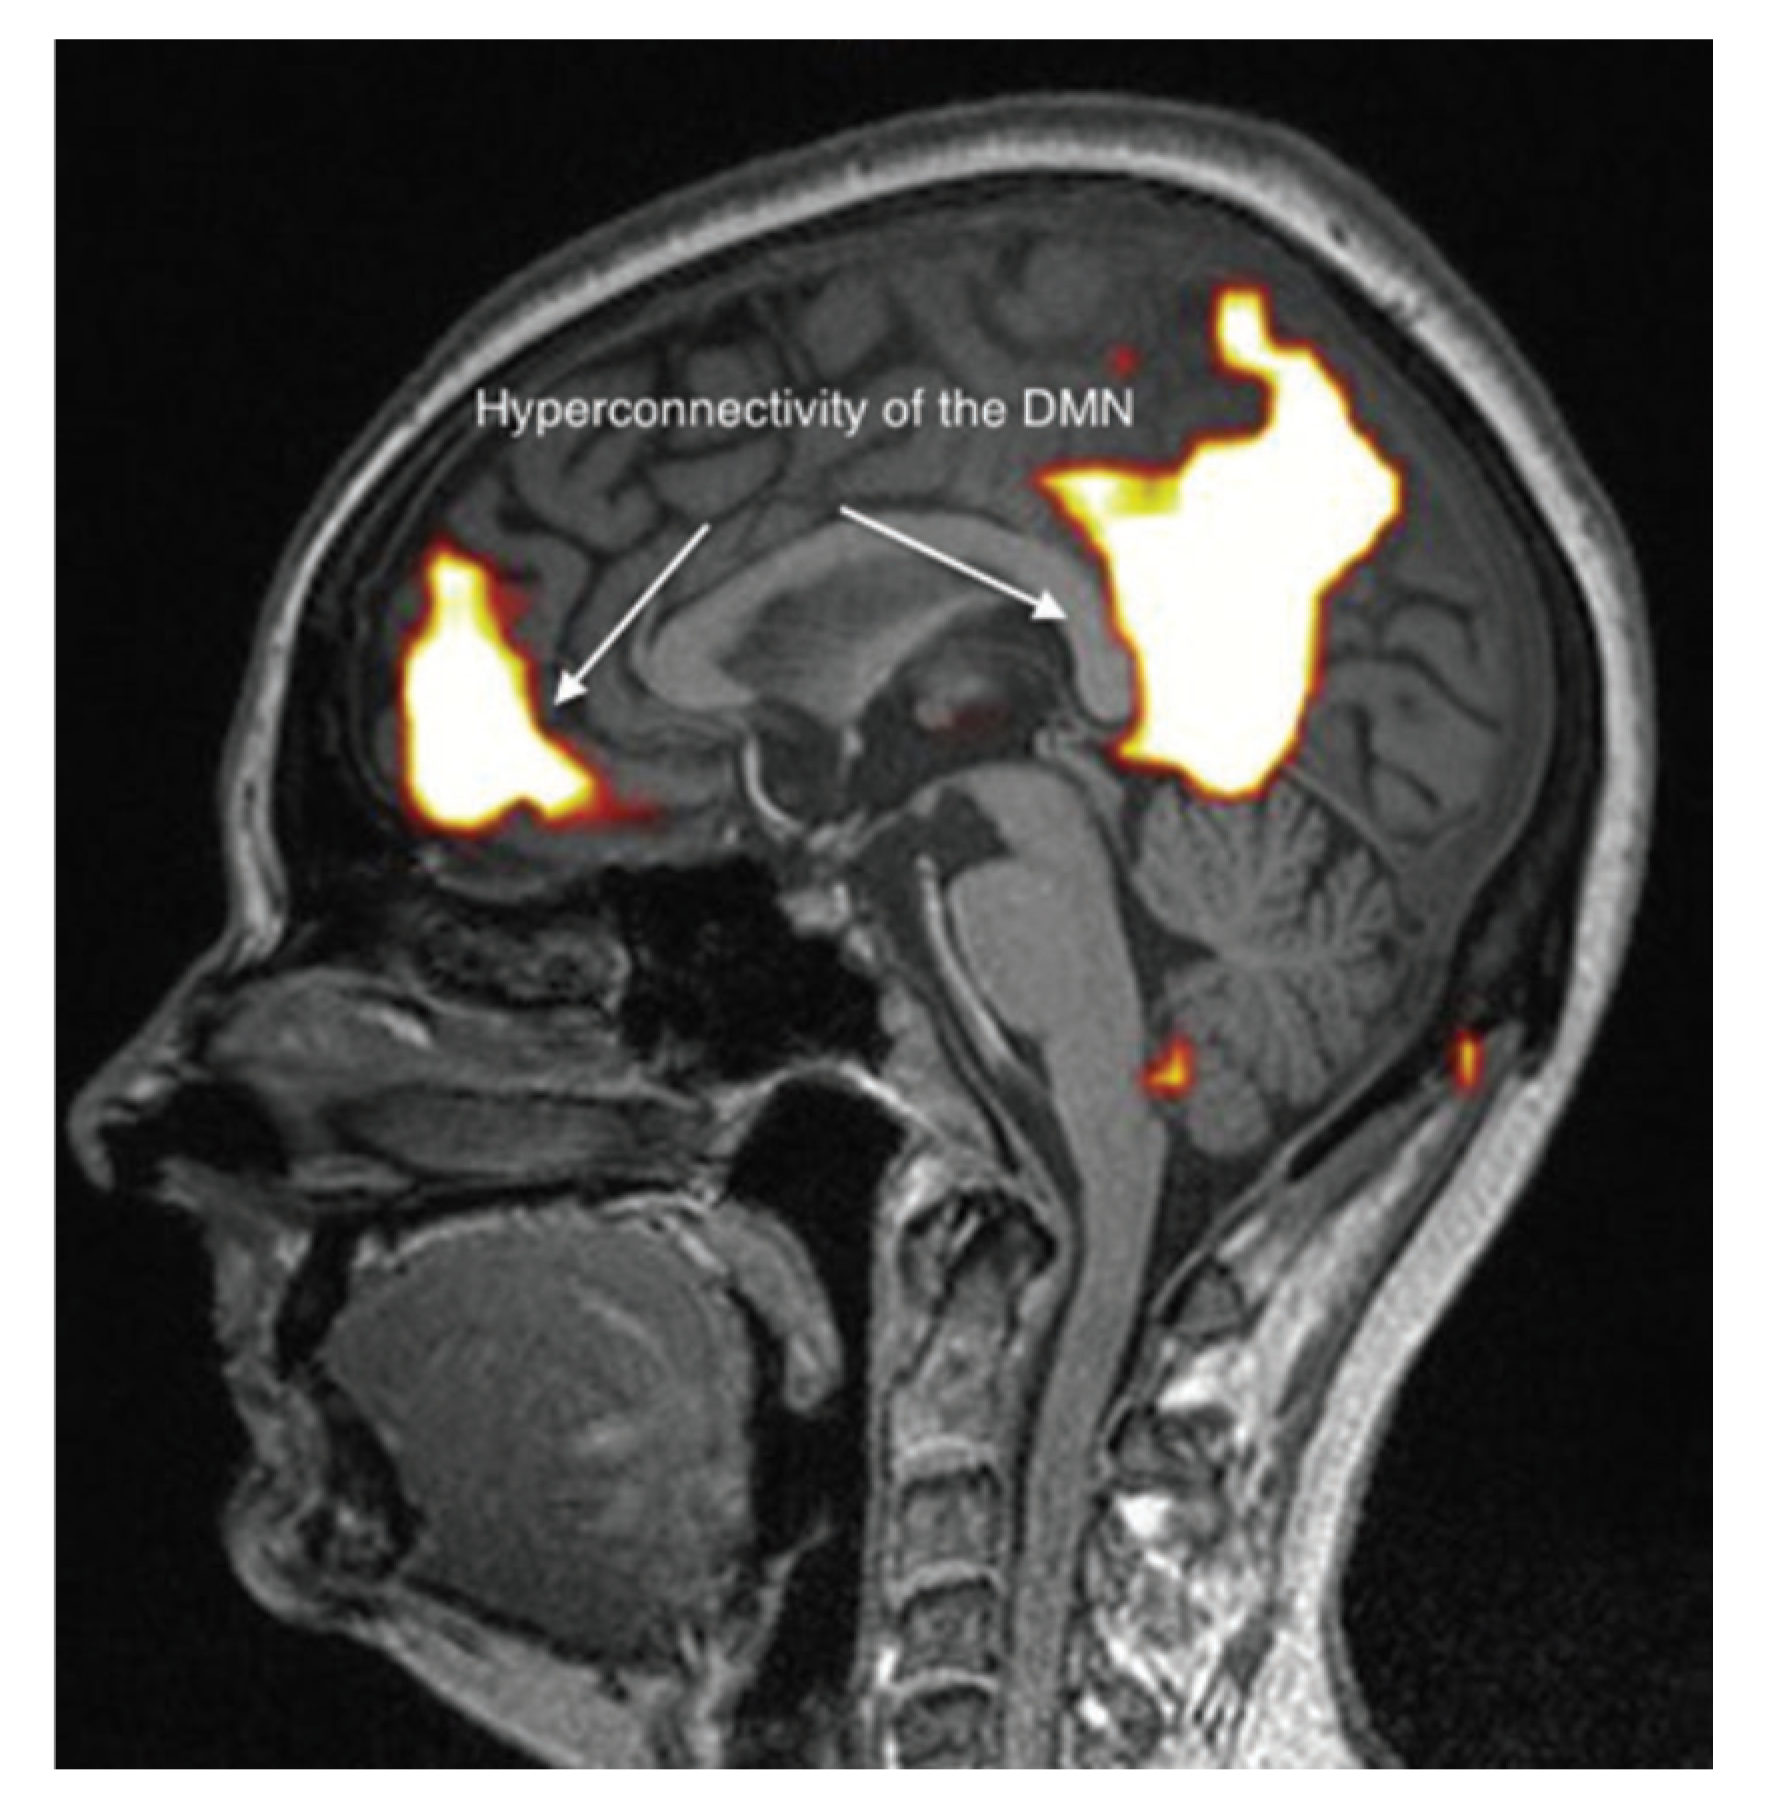

It appears, however, that these brain abnormalities are not restricted to the limbic system and the thalamus, since, by using TDU as indicated above, we showed that, in EHS and/or MCS patients, BBF in the middle cerebral arteries may be abnormal. Moreover, by using functional MRI (fMRI) in EHS patients exposed chronically to extremely low-frequency (ELF) radiation, regional BBF changes were also reported by Heuser and Heuser, but mainly in the frontal lobes, as an abnormal default mode network (DMN) (particularly as hyper-connectivity of this DMN), in association with a decrease in cerebral BBF and metabolic processes in the two so far individualized fragment hyper-connected components [31]. For example, in Figure 4, abnormal DMN is represented with fragmented hyper-connectivity of the anterior component and posterior component, which may lead to decreased BBF and/or metabolism in the bi-frontal lobes.

Figure 4. Abnormal functional MRI brain scan in patients complaining of EHS after long-term exposure to EMF, according to Reference [31].